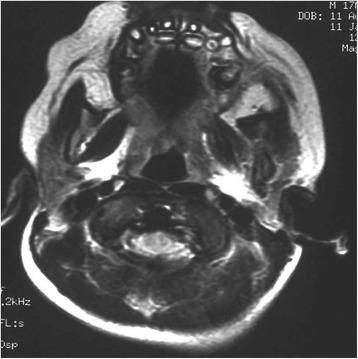

We report a case of Langerhans cell histiocytosis, which presented as an osteolytic lesion of the left pre-maxillae enclosing the deciduous incisor and canine in a 7-month-old white Italian boy. He was treated with chemotherapy. He achieved complete remission after 7 months and after 24 months no signs of recurrence were observed.

As a result of this treatment, anesthetic sequelae and loss of teeth were avoided; in addition, we prevented a loss of the vertical dimension of occlusion.